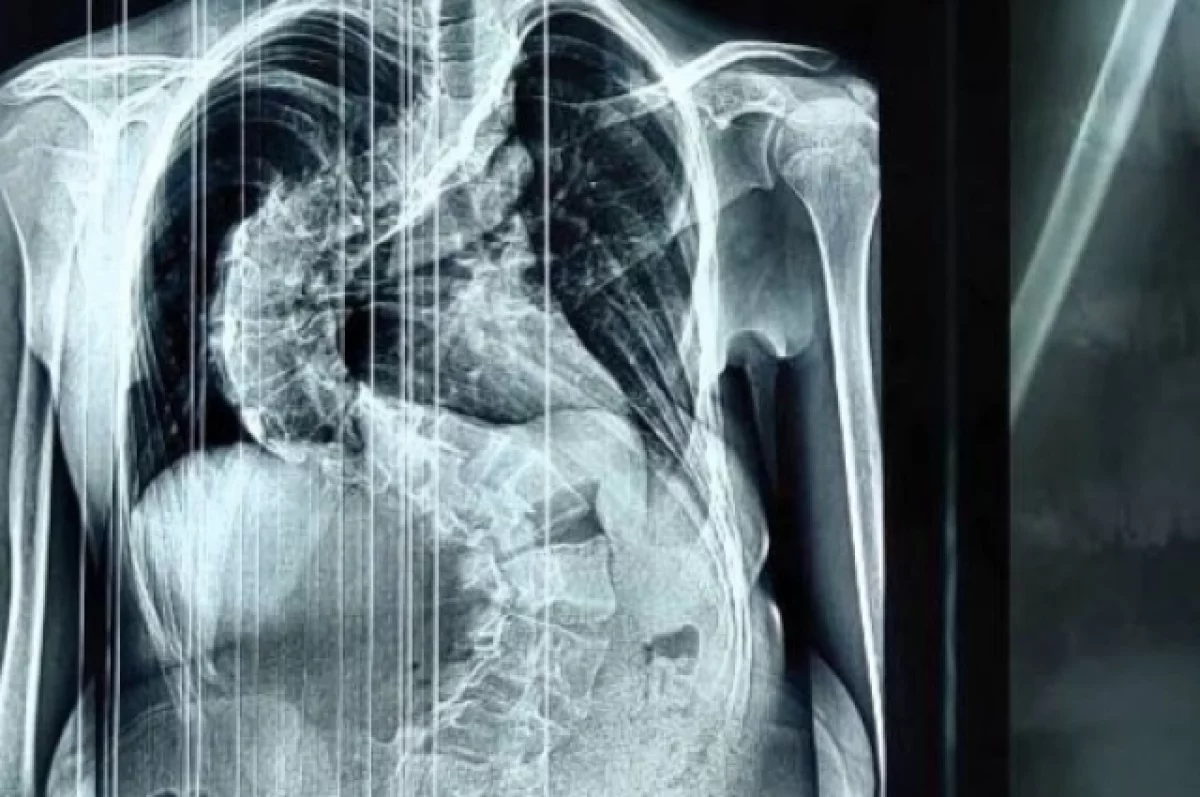

Врачи 4 часа исправляли 14-летней девочке из Кирова S-образный позвоночник

У школьницы диагностировали тяжёлую форму сколиоза.

У школьницы диагностировали серьёзную патологию — грудопоясничный сколиоз 4 степени. Болезнь развивалась с раннего школьного возраста. Единственным эффективным методом лечения на этой стадии, по словам медиков, остаётся оперативное вмешательство.

«Несмотря на молодой возраст, у девочки формировалась тяжелая, ригидная деформация. Её позвоночник был сильно деформирован и по форме напоминал латинскую букву S. При наклоне туловища вперёд в грудном отделе справа у неё определялся пологий реберный горб, а правое надплечье было выше левого на 2 см. Сколиоз такой тяжелой формы вызывает множество изменений в организме больного и приводит к необратимым последствиям для дыхательной, сердечной и других важнейших функций организма, — объяснил заведующий детским травматолого-ортопедическим отделением Алексей Молчанов.

«Перед нами стояли непростые задачи — выпрямление позвоночника и сохранение его функций. Мы установили пациентке многоопорную винто-стержневую систему: в позвонки последовательно введели специальные импланты — транспедикулярные винты, по вогнутой и выпуклой стороне деформации установили отмоделированные титановые стержни. В итоге, всё, что планировали, выполнили. Девочка получила возможность жить полноценной жизнью», — рассказал Дмитрий Курдюмов.